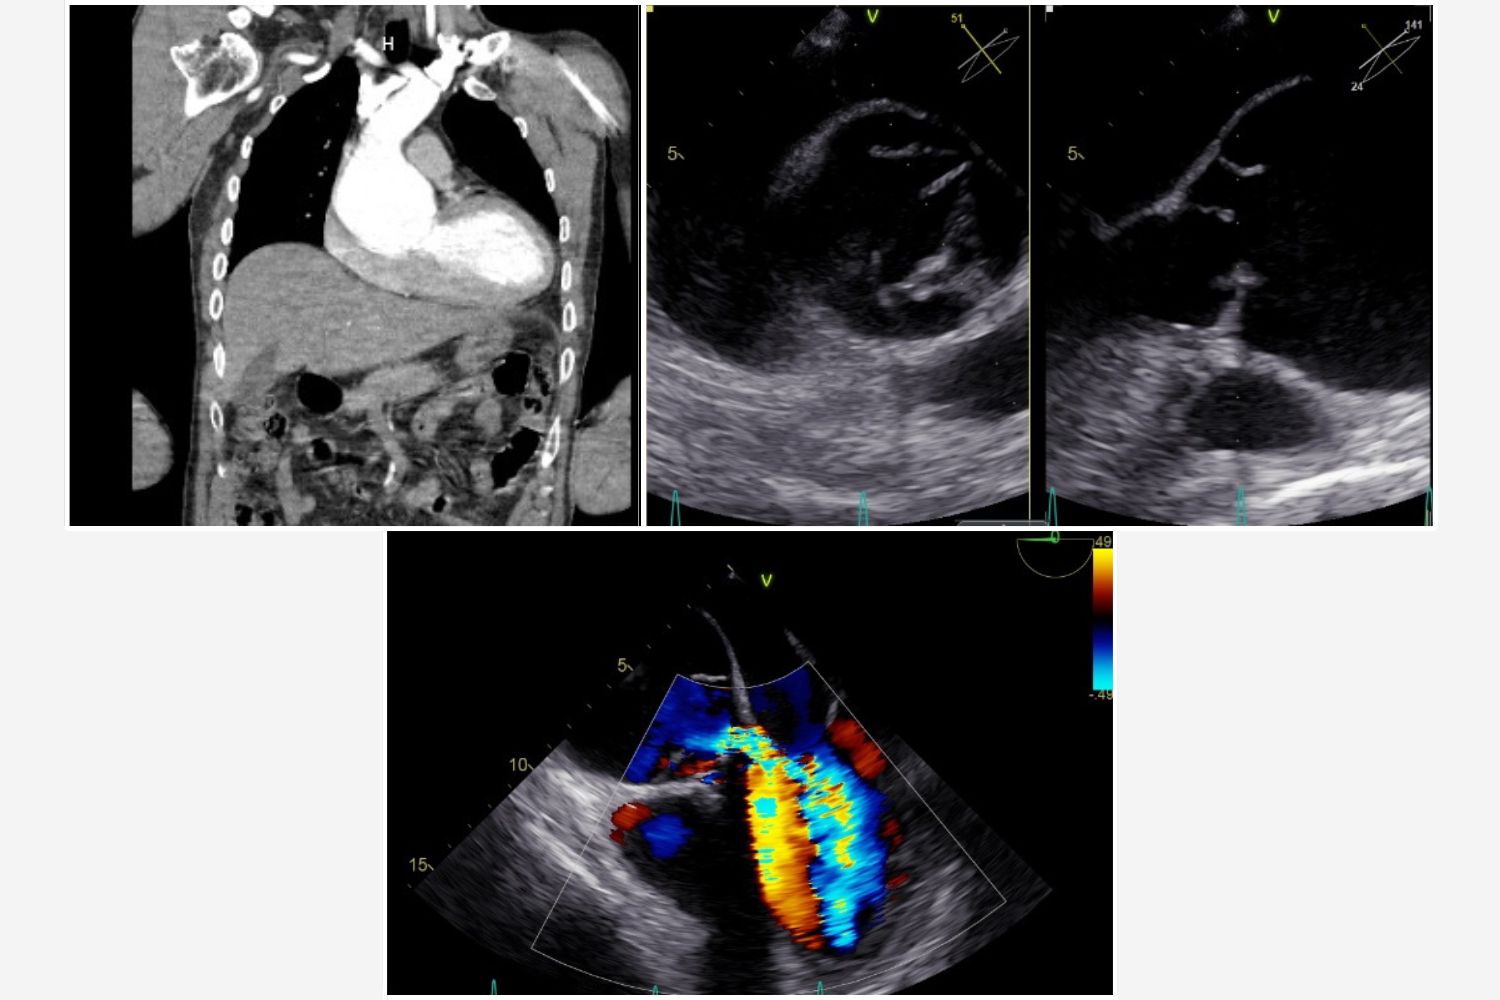

Image of the Week 21 January 2026

Image of the week

Image of the week 14 January 2026